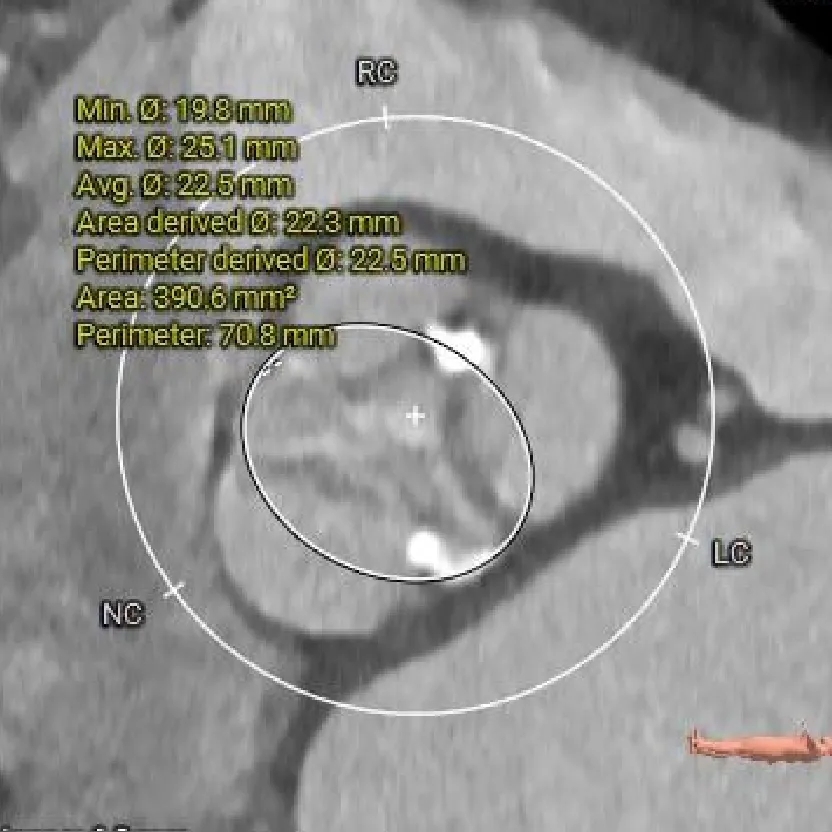

主动脉根部测量

Annulus

22.8mm

LVOT

20.4mm

钙化积分:

665mm3

SOV:

33.1*35*34.3mm

STJ:

34.5mm

AAO:

41.2mm

瓣上结构测量

瓣上2mm

23.6mm

瓣上4mm

23.8mm

瓣上6mm

22.5mm

瓣上8mm